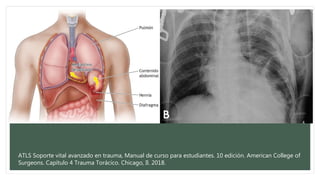

Lesión traumática del diafragma

• Son más comúnmente diagnosticadas del lado izquierdo.

• Traumas contusos: Herniaciones

• Traumas penetrantes: perforaciones.

Si se sospecha una laceración del diafragma izquierdo se puede introducir una sonda nasogástrica

si la sonda aparece en cavidad torácica en la radiografía de tórax, no es necesario realizar un

estudio contrastado.

Tx. Reparación directa.